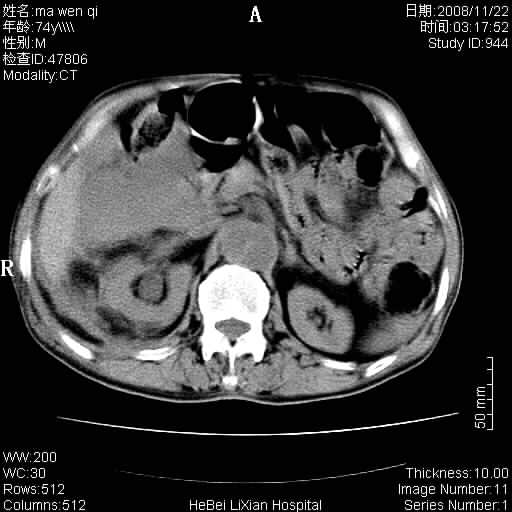

患者男 74岁.突然昏迷,休克6小时.血压70/30,头颅ct未见异常,既往体健.

补充病史,保留导尿10小时,尿袋内只有少许尿液,患者于住院后15小时后去世.

腹主动脉、双侧髂动脉夹层动脉瘤破裂出血进入腹腔。

1)考虑双侧髂动脉瘤并右侧动脉瘤破裂出血,右侧腹膜后及腹腔积血。2)双侧腹股沟疝。

1)考虑,腹主动脉、双侧髂动脉夹层动脉瘤破裂伴右侧腹膜后及腹腔积血。2)双侧腹股沟疝。

1)考虑胸、腹主动脉、双侧髂动脉瘤并右侧动脉瘤破裂出血,右侧腹膜后及腹腔积血。2)双侧腹股沟疝。